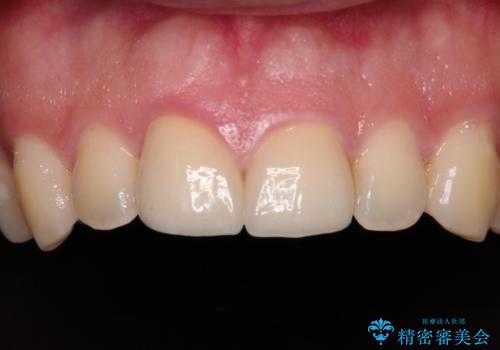

仮歯に置き換え、しみる感覚が改善されてことを確認された後に、オールセラミッククラウンにて補綴治療を行うこととしました。

術後の経過は良好でしたが、レントゲン写真にて神経が失活している時に認められる透過像のようなものが見られました。

神経の反応はあるので失活していないようですが、時間が経過すると衝撃による失活が起こることもあるため、定期的な経過観察が必要です。